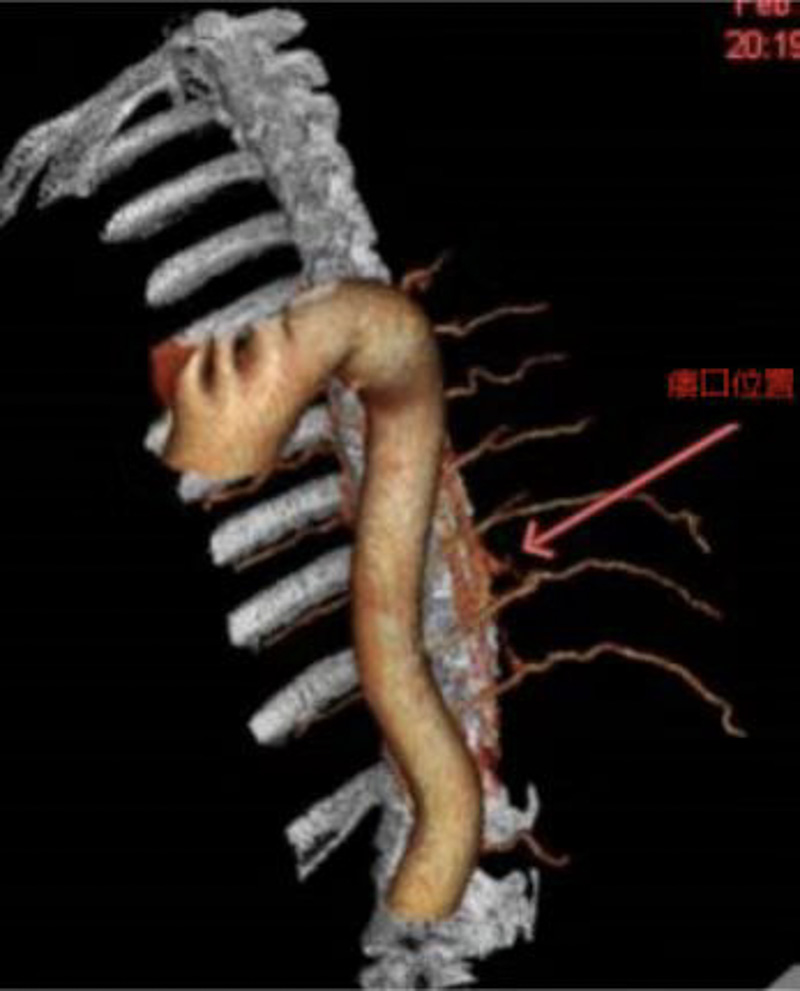

救治刻不容緩,醫院立即組織神經外科、神經內科及麻醉科等開展多學科會診,結合方先生的情況綜合判斷,為他設計了治療方案,經胸髓CTA、血管造影,明確瘺口在胸10椎體水平,決定實施顯微鏡小切口半椎板入路手術切除瘺口。

方案確定后,團隊第一時間為田先生實施了微創手術,術中可見脊髓表面較多異常迂曲擴張的回流靜脈,準確定位找到問題所在,造成下肢乏力的小瘺口僅有幾毫米,醫生在顯微鏡下精雕細琢,將異常的瘺口阻斷切除,脊髓及脊神經根保護完好,術中回流靜脈壓力明顯下降。手術僅需2.5cm小切口,磨除小部分椎板,完整保留關節突關節,不影響脊柱穩定性,無需“打釘”固定,完全保留患者的脊柱活動度。